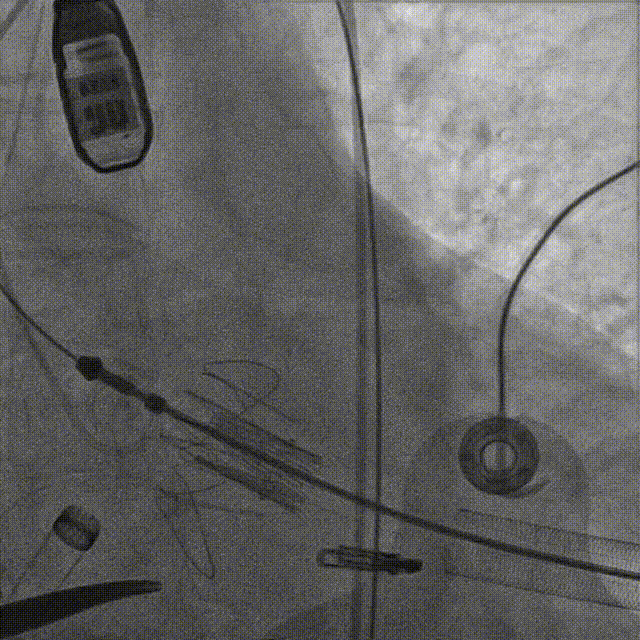

释放瓣膜后,复查根部造影,未见明显反流,瓣膜形态和位置满意,双侧冠脉显影良好:

复查超声显示主动脉瓣架深度合适、位置稳定,瓣叶启闭正常,未见明显瓣周反流:

二尖瓣反流较术前显著减少:

彻底止血,闭合心尖和外周切口,手术圆满结束。